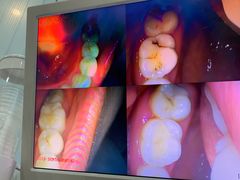

• 土豆口腔(凤凰北总店)

• -土豆口腔(凤凰北总店)